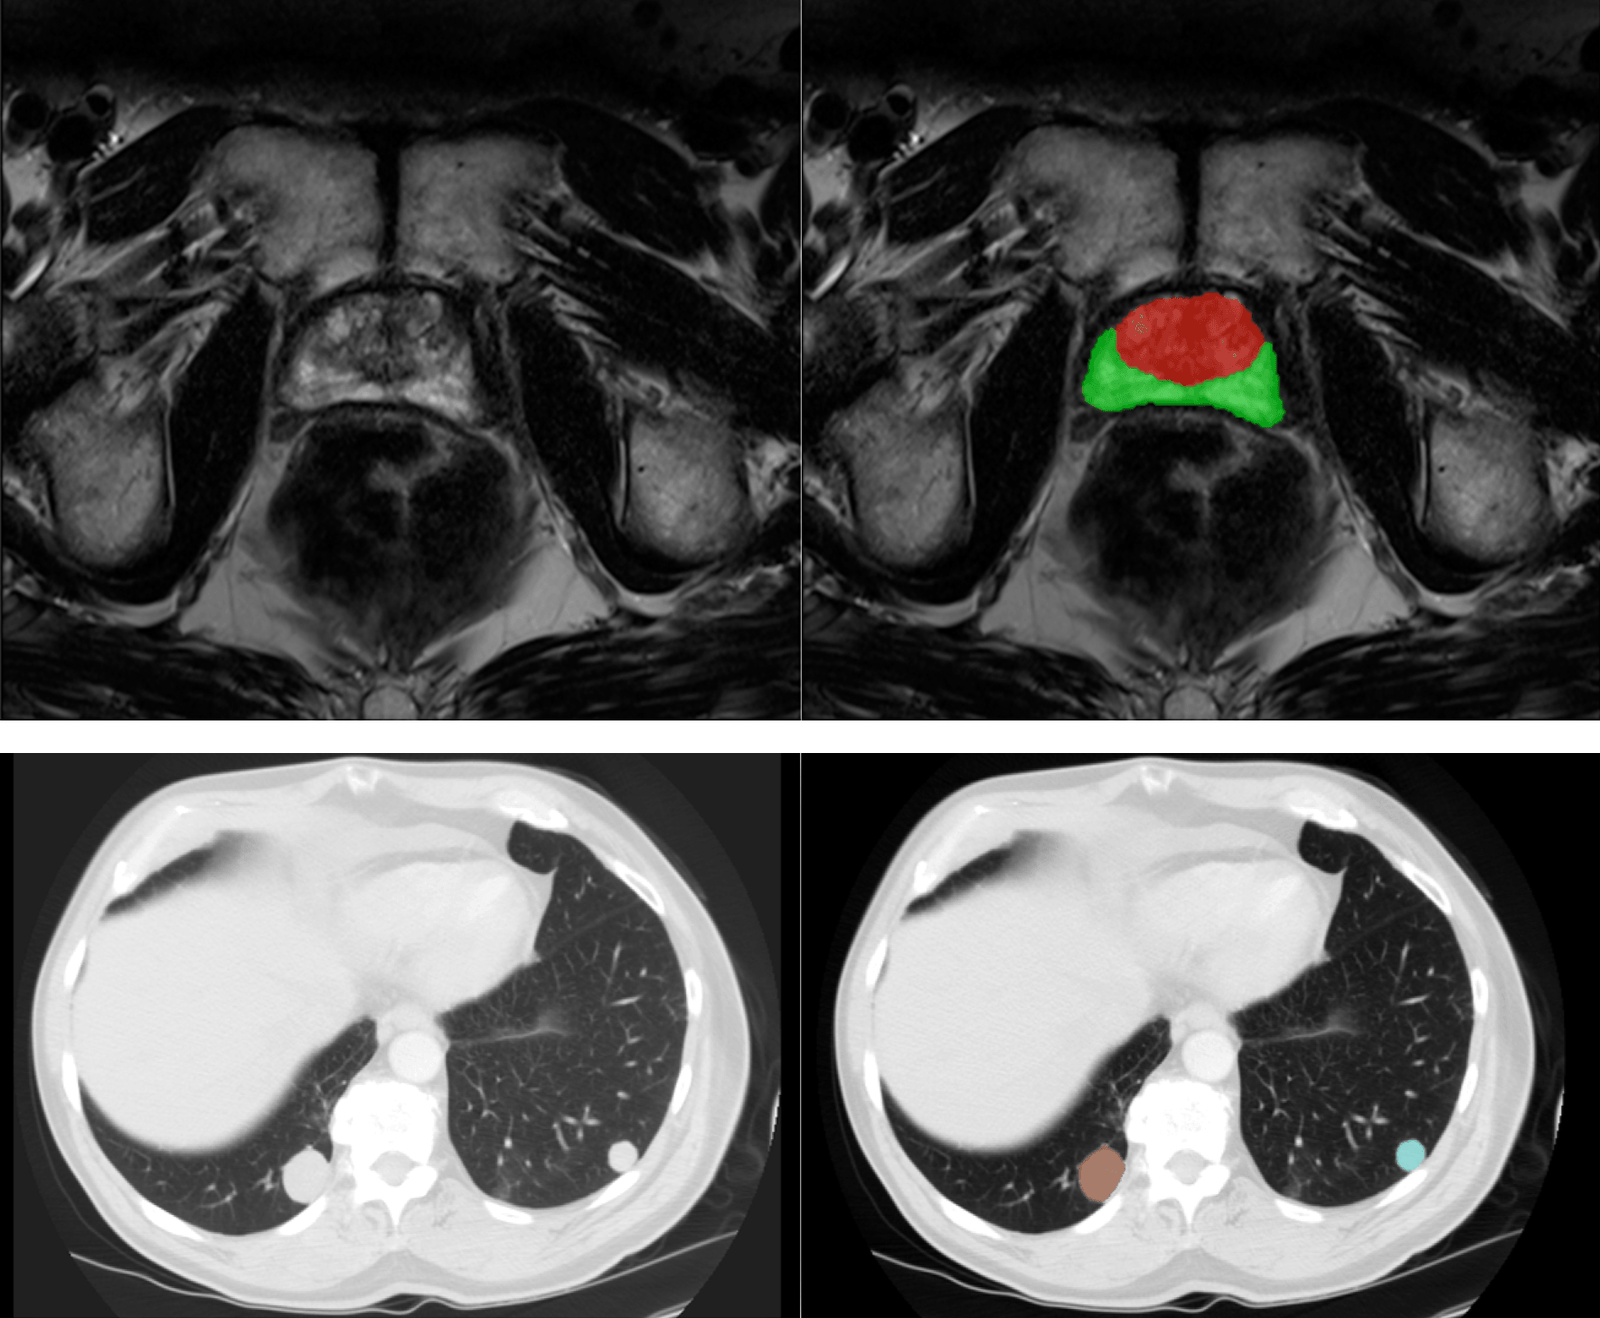

- Image segmentation algorithms: Radiologists frequently need to delineate regions of interest manually, a time-consuming endeavor. AI-powered segmentation automates this process, expediting tasks like tissue and disease characterization. Additionally, it aids in other areas, such as surgical and radiotherapy planning, where precise delineation is paramount.

- Lesion detection algorithms: Identifying anomalies within medical images can be daunting. AI assists radiologists by highlighting suspicious areas and optimizing anomaly detection and localization.